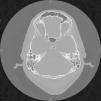

La otitis externa maligna es una infección severa cuyo diagnóstico y tratamiento continua suponiendo un reto para el clínico. El objeto de este estudio es demostrar la importancia de un análisis clínico detallado y aportar una puesta al día de las herramientas diagnósticas y terapéuticas actualmente disponibles.

Malignant otitis externa is a devastating disease that poses a diagnostic and therapeutic challenge. The objective of our study was to demonstrate the importance of detailed clinical analysis and to provide an update on the current diagnostic and therapeutic tools available.